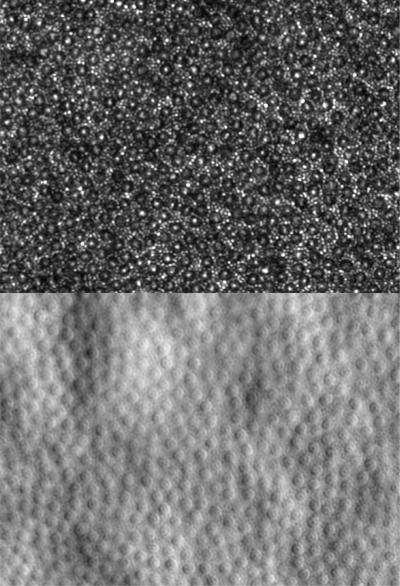

Widespread dark cones identified in a patient with oligocone trichromacy

Widespread dark cones identified in a patient with oligocone trichromacy. Confocal reflectance image (top) showing dark cones surrounded by reflective rods and non-confocal split detection image (bottom) showing the presence of cone photoreceptors at locations where dark cones are observed.